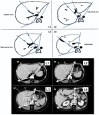

Methods: Fifty computed tomography (CT) scans obtained in subjects with normal liver were studied. Four CT scan levels were preselected: level 1 passed by the upper part of the hepatic veins; level 2 passed by the left portal vein branch division; level 3 passed by the right portal vein branch division, and level 4 passed by the gallbladder bed. Left and right tangent lines passing the liver edges were drawn and joined to the centre of the vertebra defining the TL angle. Two lines through, respectively, the plane of the middle hepatic vein and the left portal branches determined the angles of the RL, LL and LLS. Volumetric and angulometric data obtained on levels 2 and 3 in 50 different subjects were compared.

Results: Level 2 CT scans represented the most accurate way of obtaining angulometric measurements. The mean ± standard deviation (SD) angles of the TL and LL were 134 ± 12 ° and 55 ± 12 °, respectively. The mean ± SD percentages of the TL represented by the LL in angulometry and volumetry were 38 ± 7% and 36 ± 6%, respectively (non-significant difference). The mean ± SD percentages of the TL represented by the LLS in angulometry and volumetry were 25 ± 4% and 20 ± 3%, respectively (P < 0.05). The mean ± SD overestimation of the percentage of the TL represented by the LLS in angulometry was 2.7 ± 7.0%.